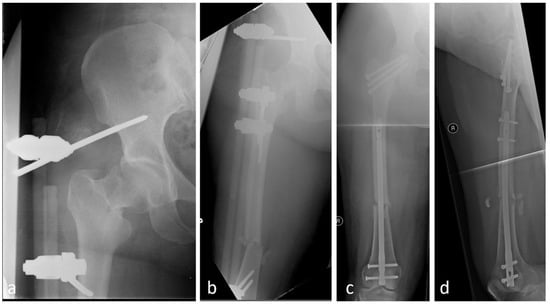

5.3. Reconstruction With or Without Additional Cables and Plates

- Dietze, C.; Brand, A.; Friederichs, J.; Stuby, F.; Schneidmueller, D.; von Rüden, C. Results of revision intramedullary nailing with and without auxillary plate in aseptic trochanteric and subtrochanteric nonunion. Eur. J. Trauma Emerg. Surg. 2022, 48, 1905–1911. [Google Scholar] [CrossRef] [PubMed]